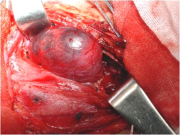

| 09:33, 7 בנובמבר 2012 | פאוכרומוציטומה614.png (קובץ) |  |

185 קילו־בייטים | Motyk | 1 | |